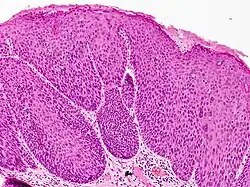

Bowenoid papulosis is a cutaneous condition characterized by the presence of pigmented verrucous papules on the body of the penis.[1]: 730 [2]: 408 They are associated with human papillomavirus, the causative agent of genital warts.[3]

Bowenoid papulosis diagnosis requires a history, histologic examination, and clinical description of the condition.[9]